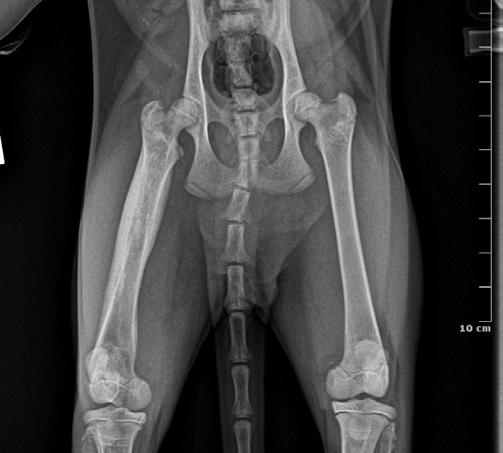

Four weeks later, Hotch was presented with marked lameness and a firm marked swelling of his left antebrachium. There were no obvious wounds or scabs, although he was hyperthermic. He was admitted for radiographs (see images) under sedation (dexmedetomidine 5µg/kg, methadone 0.3 mg/kg).

1

Radiographs showed signs of acute suppurative osteomyelitis, likely bacterial. This has a characteristic appearance in kittens, as the periosteum is not so strongly attached to the bone cortex, and the neutrophilic exudate lifts the periosteum, which then makes a florid new bone response ( blue arrow). Usually, these infections arise after a bite wound. The periosteal new bone formation is florid. Patchy portions of cortical bone lysis (yellow arrow) are also evident towards the centre of the lesion. At this stage we contacted Dr Richard Malik at the CVE as I had never seen anything like this before. Richard was also concerned about mild nutritional secondary hyperparathyroidism (NSH) due to the bone cortices appearing pale (osteopaenic), with an area of increased relative radiodensity immediately next to the growth plates (orange arrow). In NSH, the only normal bone is that laid down by endochondral ossification at the growth plates (and in this case—where new bone is laid down to wall off the infected bone), the rest of the skeleton is being broken down by osteoclasts under the direction of PTH.

Figure 1. Radiographs of the affected limb at presentation

Note the generalised mild osteopaenia, with narrow lamellated cortices of many of the long bones.